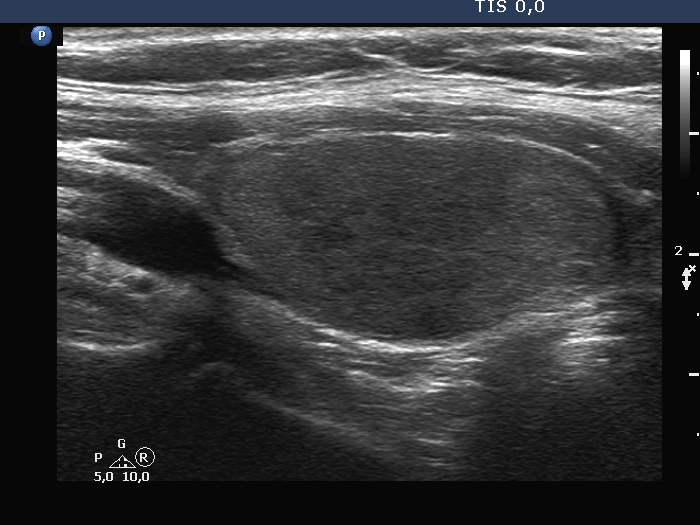

Ultrasonography. Both previously described nodules have significantly increased in size. The dimensions of the right nodule were 25x17x36 mm, width, depth, length, respectively.

The nodule, which was previously described in the left lobe, seemed to be located in the isthmus. The dimensions of this lesion were 36x18x40 mm, width, depth, length, respectively. Except for the significant increase in size, the pattern of the nodules remained unchanged. Several small, hypoechoic discrete lesions were found in the left lobe.Cytology was performed form both nodules and resulted in follicular tumor and benign cystic-colloid goiter, right and left nodule, respectively. The cyst could not be emptied, only a small amount of brown fluid could be aspirated.